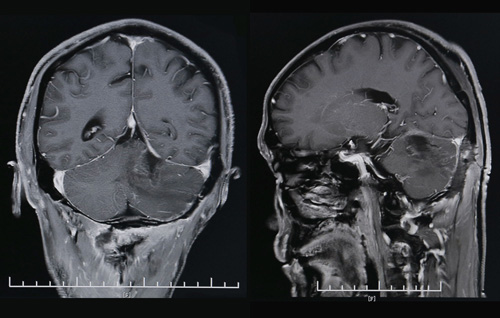

术后CT影像显示,肿瘤已经消失

这台难度较高的手术由神经外科主任沈建康教授亲自操刀。从切开头皮到止血缝合,总共历时约4小时。“手术的关键是找到和完整切除血管性肿瘤。”沈建康教授解释道,囊肿被穿刺后囊液流出,瘪下去的囊肿就会使血管性肿瘤“隐身”于周围脑组织中,若不加以彻底摘除,仍具有危害性。这对于手术医师的技术和经验是极大的考验。